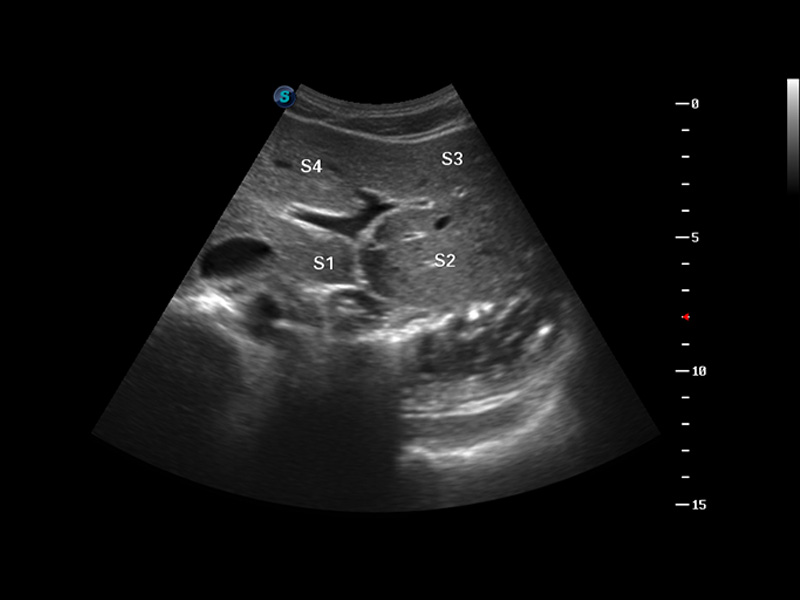

S8 EXP便携式彩色多普勒超声诊断仪是诸侯快讯官网研发的高端全身应用型便携彩超。高通道的VIS平台融合可视化(Visual)、智能化(Intelligent)和人性化(Smart)的特点,配以诸侯快讯官网自主研发生产的探头大家族,使您能够快速、准确的获得病人信息,提高工作效率的同时减轻疲劳。

μ-Scan微米成像

谐波成像

空间复合成像

3D/4D成像